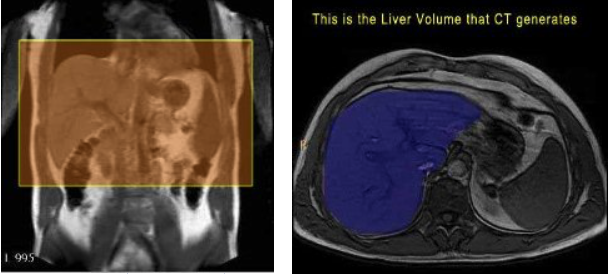

- The Abdomen scans are breath-holds. You can change parameters as needed to get a single acquisition. HOWEVER - you CANNOT change the slice thickness / gap. (The slice thickness/gap need to add up to 10 - i.e. 8 skip 2, 9 skip 1, etc.) When done let CT know that you need liver volumes calculated on this subject.

| AX | T1 | TR only | YES | Angle as normal, be sure to cover the entire mass/tumor/pit | |

| AX | T1 | TR only | YES | Angle as normal, be sure to cover the entire mass/tumor/pit |

Notes: These scans are breath-holds. You can change parameters as needed to get a single acquisition. HOWEVER - you CAN NOT change the slice thickness / gap. (The slice thickness/gap need to add up to 10 - i.e. 8 skip 2, 9 skip 1, etc.) When done let CT know that you need liver volumes calculated on this subject.